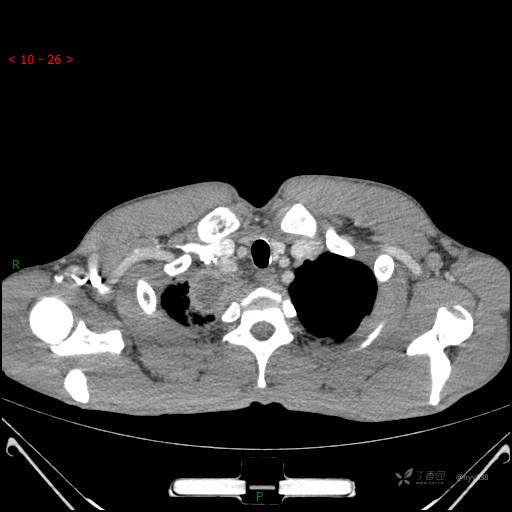

辅助检查:CT

胸部CT平扫